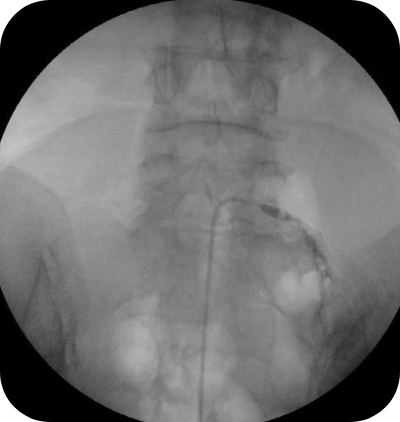

척추 꼬리뼈 부위에 국소마취를 한 후 C-Arm을 통한 X-ray 투시장치로 병변을 직접 보면서 풍선 기능이 탑재된 특수 카테터를 협착 부위에 삽입하여 풍선의 압력을 이용하여 좁아진 신경 구멍을 확장하며, 카테터를 통해 약물(고농도 식염수, 유착 방지제 등)을 주입하여 척추 신경 주위에 염증 부종을 제거합니다.